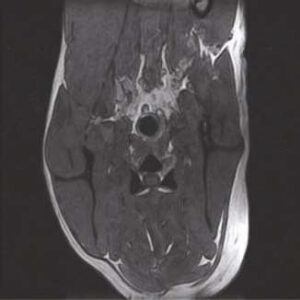

The PANION PRO comes with the double-pole open magnet design with a wide opening gap of 40 cm to accommodate large-sized animals on an efficient patient handling platform, the strongest gradient amplitude at 33mT/m and slew rate of 90 T/m/s, among all other open MRI systems, resulting in high spatial resolution of images in short scan time. The 6-direction patient table permits iso-centre imaging of all anatomical regions.

Clinical Images